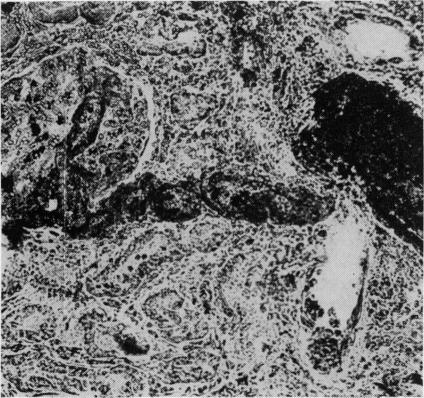

Bilateral cortical necrosis of the kidneys following snakebite.

Postgrad Med J. 1970 Jul;46(537):449-51. doi: 10.1136/pgmj.46.537.449.

https://cdn.ncbi.nlm.nih.gov/pmc/blobs/ee00/2467058/f3b02d0c8d1e/postmedj00355-0049-b.jpg

https://cdn.ncbi.nlm.nih.gov/pmc/blobs/ee00/2467058/6aa95fd270fc/postmedj00355-0049-a.jpg